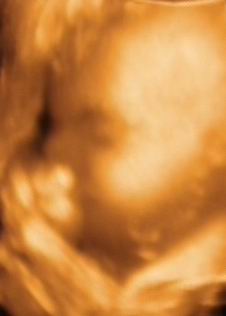

A második képen nyitva van a szeme is